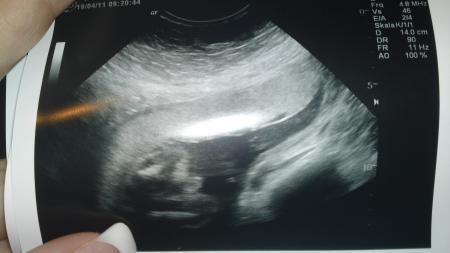

Und hier Bild 2

Bild zu

Auf dem ersten Bild ist Links ein kleines weißes Kreuz, direkt da drüber solls wohl sein, wie gesagt ich erkenn darauf auch net viel :D Ich weiß aber auch nicht wie zum Vergleich ein Jungen-Ultraschall aus dieser Perspektive Aussehen soll... Aber ich hab auch die Vermutung da kein Schniedelchen drauf zu sehen

also bei nem Jungen würdest Du eindeutig den Hodensack und den Pippimann sehen, den seh ich bei Deinen Bildern aber nicht ;o)

Also ich finde man kann es schwer erkennen. Wir bekommen ja ein Mädchen und bei uns konnte man eindeutig ``striche`` sehen. Aber ich würde auch sagen das es ein Mädchen wird. Den bei einem Jungen müsste man ja defintiv mehr sehen (-; Finde das Verhalten von deinem FA echt unmöglich Liebe Grüße